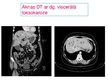

Viscerālā forma:

Pneimonija

Brohiālā astma

Endokardīts, miokardīts, sirds nepietikamība

Granulēmas orgānos un audos